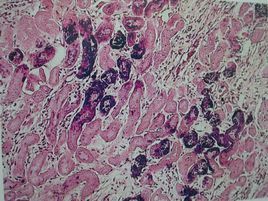

③ 組織液可以滲入毛細淋巴管形成淋巴(毛細淋巴管僅由單層內皮細胞構成,無基膜和外周細胞,細胞復瓦狀扣合,管壁通透性大於毛細血管,一般不容易進毛細血管的大分子物質,蛋白質、細菌、癌細胞等易進入其內)。